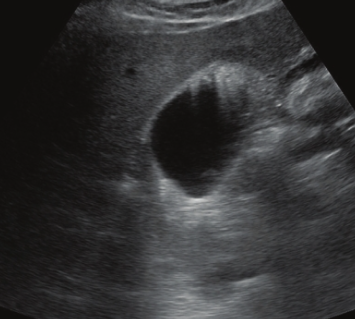

담낭염은 담낭의 벽에 염증이 발생하는 질환으로, 이는 대부분 담석증 때문에 발생합니다. 담석증이란 담즙에 포함된 콜레스테롤이나 빌리루빈 같은 물질이 응고되어 돌처럼 굳어진 상태를 말하며, 이러한 담석이 담낭의 출구를 막게 되면 담즙이 제대로 배출되지 못하고 담낭 내에 고이게 됩니다.

이 상태가 지속되면 담낭 내부의 압력이 증가하게 되고, 이는 결국 염증을 유발하게 됩니다. 염증이 진행됨에 따라 담낭 벽이 두꺼워지고, 이 상태가 심해지면 감염으로 이어질 수도 있습니다.